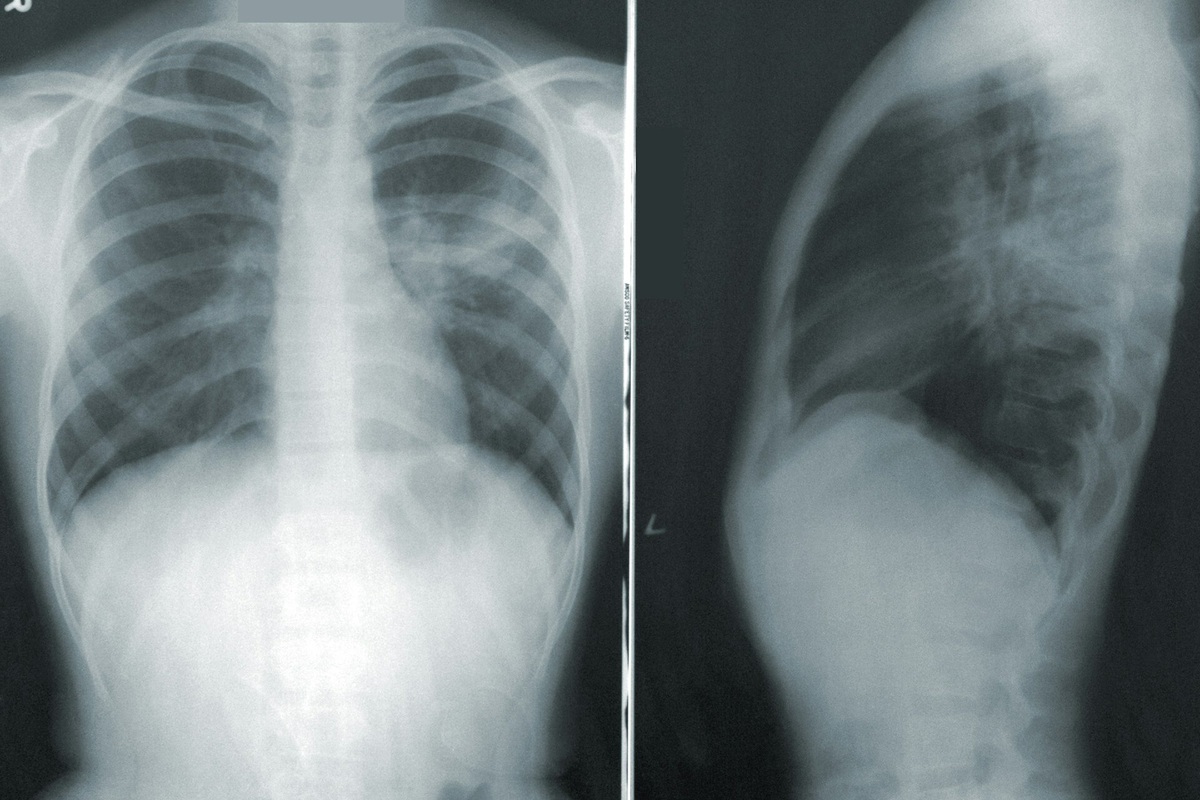

Человеческие легкие начинают сдавать позиции раньше, чем считалось. Согласно новому исследованию, максимальная функция легких достигается примерно в 20 лет, а затем начинается неизбежный спад. В новом исследовании, опубликованном в The Lancet Respiratory Medicine, ученые из Барселонского института глобального здоровья (ISGlobal) проанализировали данные 30 тысяч человек от 4 до 82 лет из Европы и Австралии и пришли к неожиданному выводу: человеческие легкие достигают максимума рано, в 20–23 года, а затем сразу начинают слабеть. Раньше считалось, что после достижения пика легочная функция держится на плато до 40 лет. Но новая работа опровергает эту модель. По словам авторов, предыдущие выводы основывались на точечных данных, а не на длительном наблюдении. В ходе анализа ученые выделили два основных этапа развития легких: стремительный рост в детстве и плавный до 20–23 лет. А вот фазы стабильности – не нашли вовсе. Особенно интересными оказались различия в воздействии на легкие таких факт

В новом исследовании, опубликованном в The Lancet Respiratory Medicine, ученые из Барселонского института глобального здоровья (ISGlobal) проанализировали данные 30 тысяч человек от 4 до 82 лет из Европы и Австралии и пришли к неожиданному выводу: человеческие легкие достигают максимума рано, в 20–23 года, а затем сразу начинают слабеть.